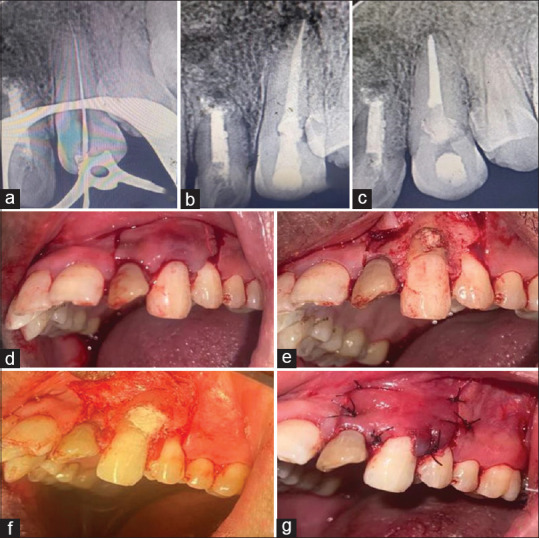

牙齿吸收;内部和外部,偶尔发生作为牙槽器感染的炎症反应。根据吸收的类型、病因和发现根吸收缺陷的阶段,提出了不同的治疗方案。本病例报告展示了通过使用生物陶瓷密封剂(BioRoot RCS)的非手术根管治疗和使用Biodentine重建吸收缺陷来治疗广泛的炎症性内外根吸收。在1、3、6和12个月的随访中,临床和影像学证据显示根尖周愈合、牙根吸收停止和牙周再植的迹象。锥束计算机断层扫描在诊断、决策和治疗计划中起着至关重要的作用,从而成功地管理这些有牙髓-牙周受累的病例。在12个月的随访中,临床和放射学结果支持,使用生物陶瓷材料可以成功地治疗广泛的牙根吸收和牙周组织累及的病例。

Tooth resorption; both internal and external, occasionally occurs as an inflammatory response of the dentoalveolar apparatus to infection. Depending on the type of resorption, etiology, and the stage at which root resorption defect is detected, different treatment regimens have been proposed. This case report demonstrates the management of extensive inflammatory combined internal and external root resorption by nonsurgical endodontic therapy using a Bioceramic sealer (BioRoot RCS) and surgical reconstruction of resorptive defect using Biodentine. On follow-up at 1, 3, 6, and 12 months, clinical and radiographic evidence revealed signs of periapical healing, arrested root resorption, and periodontal reattachment. The inclusion of cone beam computed tomography plays a crucial role in diagnosis, decision-making, and treatment planning and thus successful management of such cases having Endodontic-Periodontal involvement. As supported by clinical and radiographic findings at 12-month follow-up, treatment of cases with extensive root resorption and associated involvement of periodontium can be successfully done using bioceramic materials.